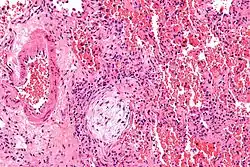

![]() | |

| Micrograph showing a Masson body (off center left/bottom of the image – pale circular and paucicellular), as may be seen in cryptogenic organizing pneumonia. The Masson body plugs the airway. The artery associated with the obliterated airway is also seen (far left of the image). H&E stain. | |

Biopsy findings in patients with organizing pneumonia consist of loose connective tissue plugs involving the alveoli, alveolar ducts and bronchioles. The loose connective tissue plugs occupying the alveolar spaces often connect to other connective tissue plugs in nearby alveoli via the pores of Kohn creating a characteristic butterfly pattern on histology.[9] There is usually minimal to no interstitial inflammatory changes in biopsies of organizing pneumonia.[9]

Histologically, cryptogenic organizing pneumonia is characterized by the presence of polypoid plugs of loose organizing connective tissue (Masson bodies) within alveolar ducts, alveoli, and bronchioles.